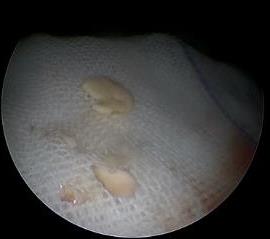

摘要:目的 探讨耳内镜下耳屏软骨-软骨膜鼓膜修补术后的短期疗效。方法 回顾性分析2019年9月-2022年8月该院收治的78例鼓膜穿孔患者的临床资料,患者均采用耳内镜下鼓膜修补术。术后随访3个月,观察鼓膜形态和穿孔愈合情况,记录内镜图像、干耳时间、术前术后听力及耳鸣情况,以及外耳道狭窄等并发症的发生率。结果 术后3个月,鼓膜穿孔愈合率为97.44%(76/78),愈合良好,平均气导听阈较术前明显改善,气骨导间距较术前明显缩小,耳鸣较术前明显改善,差异均有统计学意义(P<0.05)。干耳时间为(4.21±1.12)周。术后出现肉芽5例,再穿孔2例,真菌感染2例,术腔感染、耳屏感染、外耳道狭窄和切口瘢痕各1例,所有患者术后均未发生面神经麻痹和感音神经性聋等严重并发症。结论 耳内镜下耳屏软骨-软骨膜鼓膜修补术是一种安全、有效的手术方法。根据术后愈合规律、内镜下鼓膜和外耳道形态特征,可为鼓膜修补术后正常中耳转归和并发症的诊疗,提供临床参考。